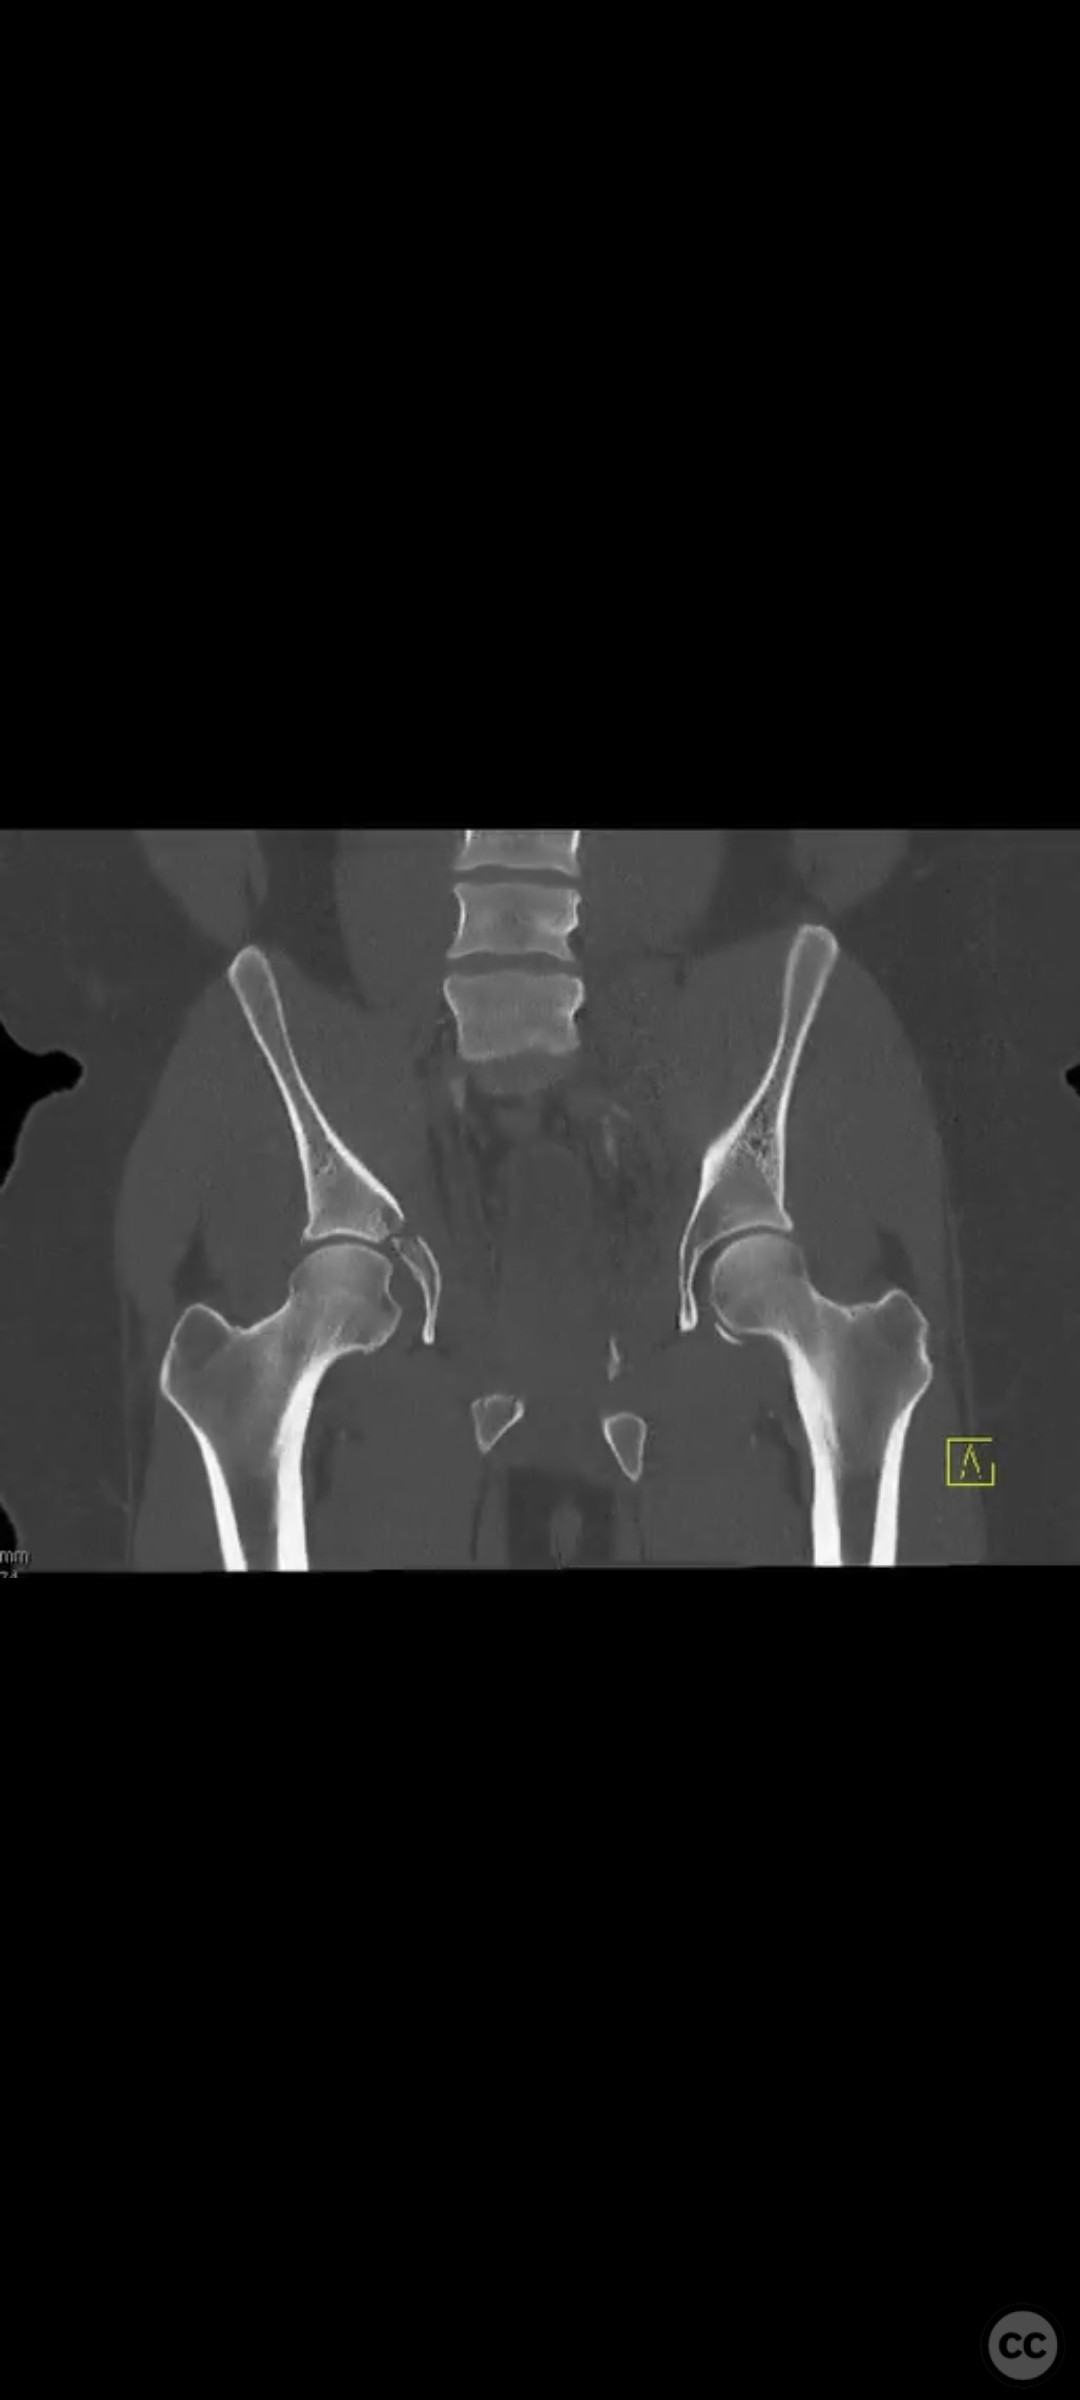

Clinical and radiological findings:  The patient presented with a highly unstable pelvic ring injury and a transverse acetabulum fracture, accompanied by a bladder injury. The bladder injury was addressed emergently with a low vertical midline Pfannenstiel incision for repair, followed by the placement of a low right-sided suprapubic catheter. Radiological imaging confirmed the transverse acetabular fracture and disruption of the left sacroiliac joint, along with a displaced sacral fracture.

Planning remarks:  The preoperative plan involved a staged approach to address the combined injuries. Initially, the focus was on stabilizing the pelvic ring to provide a stable base for subsequent acetabular reconstruction. The left sacroiliac joint disruption was to be reduced and stabilized first, followed by lag screw fixation of the displaced sacral fracture. Additional screws were planned as anatomical corridors allowed. An external fixator was considered to support the posterior ring stabilization. The second stage involved open reduction and internal fixation (ORIF) of the acetabulum through a Kocher-Langenbeck approach, with potential anterior column fixation via the modified Stoppa approach if necessary.